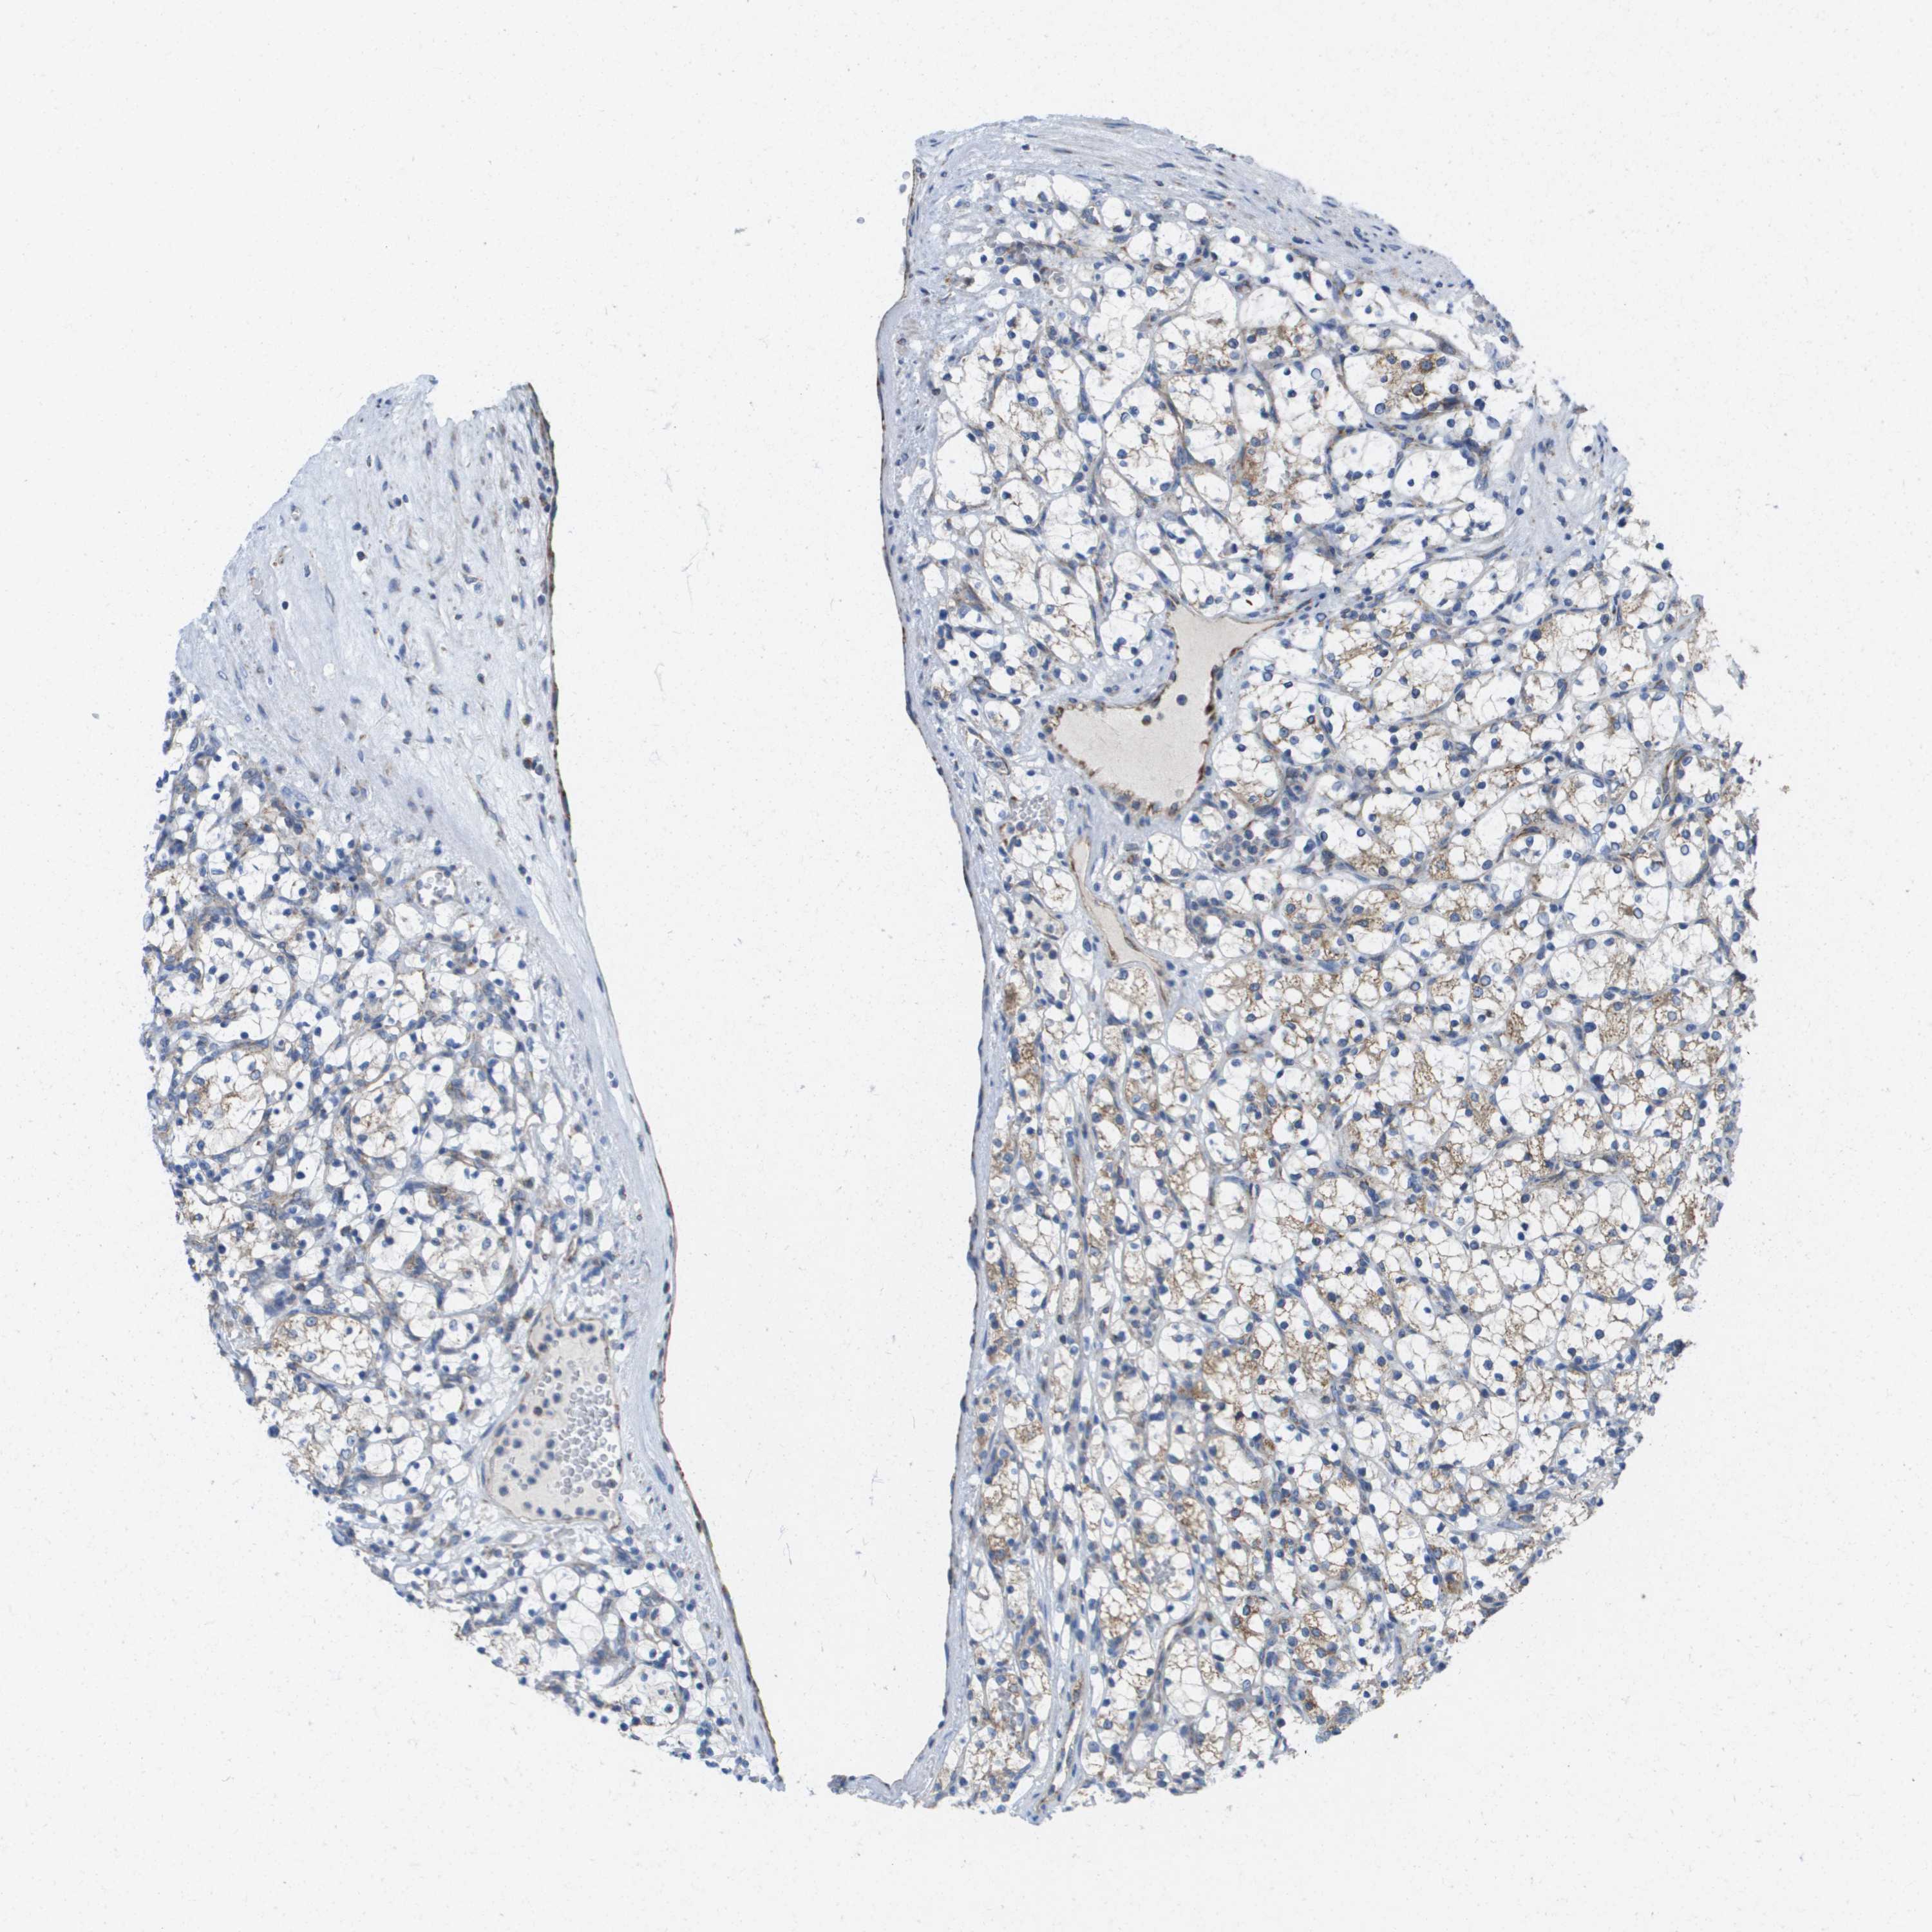

KIDNEY RENAL CLEAR CELL CARCINOMA (VALIDATION) - Interactive survival scatter ploti

The Survival Scatter plot shows the clinical status (i.e. dead or alive) for all individuals in the patient cohort, based on the same data that underlies the corresponding Kaplan-Meier plots. Patients that are alive at last time for follow-up are shown in blue and patients who have died during the study are shown in red.

The x-axis shows the expression levels (FPKM) of the investigated gene in the tumor tissue at the time of diagnosis. The y-axis shows the follow-up time after diagnosis (years). Both axes are complimented with kernel density curves demonstrating the data density over the axes. The top density plot shows the expression levels (FPKM) distribution among dead (red) and alive patients (blue). The right density plot shows the data density of the survived years of dead patients with high and low expression levels respectively, stratified using the cutoff indicated by the vertical dashed line through the Survival Scatter plot. This cutoff is automatically defined based on the FPKM cutoff that minimizes the p-score. The cutoff can be changed by dragging the vertical line or by entering a cutoff value in the square labeled "Current cut-off".

Under the Survival Scatter plot the p-score landscape (black curve; left axis) is shown together with dead median separation (red curve; right axis). Dead median separation is the difference in median mRNA expression between patients who have died with high and low expression, respectively. It is calculated as follows: median FPKM expression of dead patients with high expression - median FPKM expression of dead patients with low expression. This is intended to aid the user in visually exploring custom cutoffs and the associated p-scores and dead median separation.

Individual patient data is displayed and can be filtered by clicking on one or more of the category buttons on the top of the page. Categories describing expression level and patient information include: high, low, alive, dead, female, male and tumor stages. The scale of the x-axis can be toggled between linear and log-scale by clicking on the "x log" button. Mouse-over function shows TCGA ID, patient information and mRNA expression (FPKM) for each patient.

& Survival analysisi

Kaplan-Meier plots summarize results from analysis of correlation between mRNA expression level and patient survival. Patients were divided based on level of expression into one of the two groups "low" (under cut off) or "high" (over cut off). X-axis shows time for survival (years) and y-axis shows the probability of survival, where 1.0 corresponds to 100 percent.

FIS1 is not prognostic in Kidney Renal Clear Cell Carcinoma (validation)

: 159.34

Average pTPM 134.7

Number of samples 100